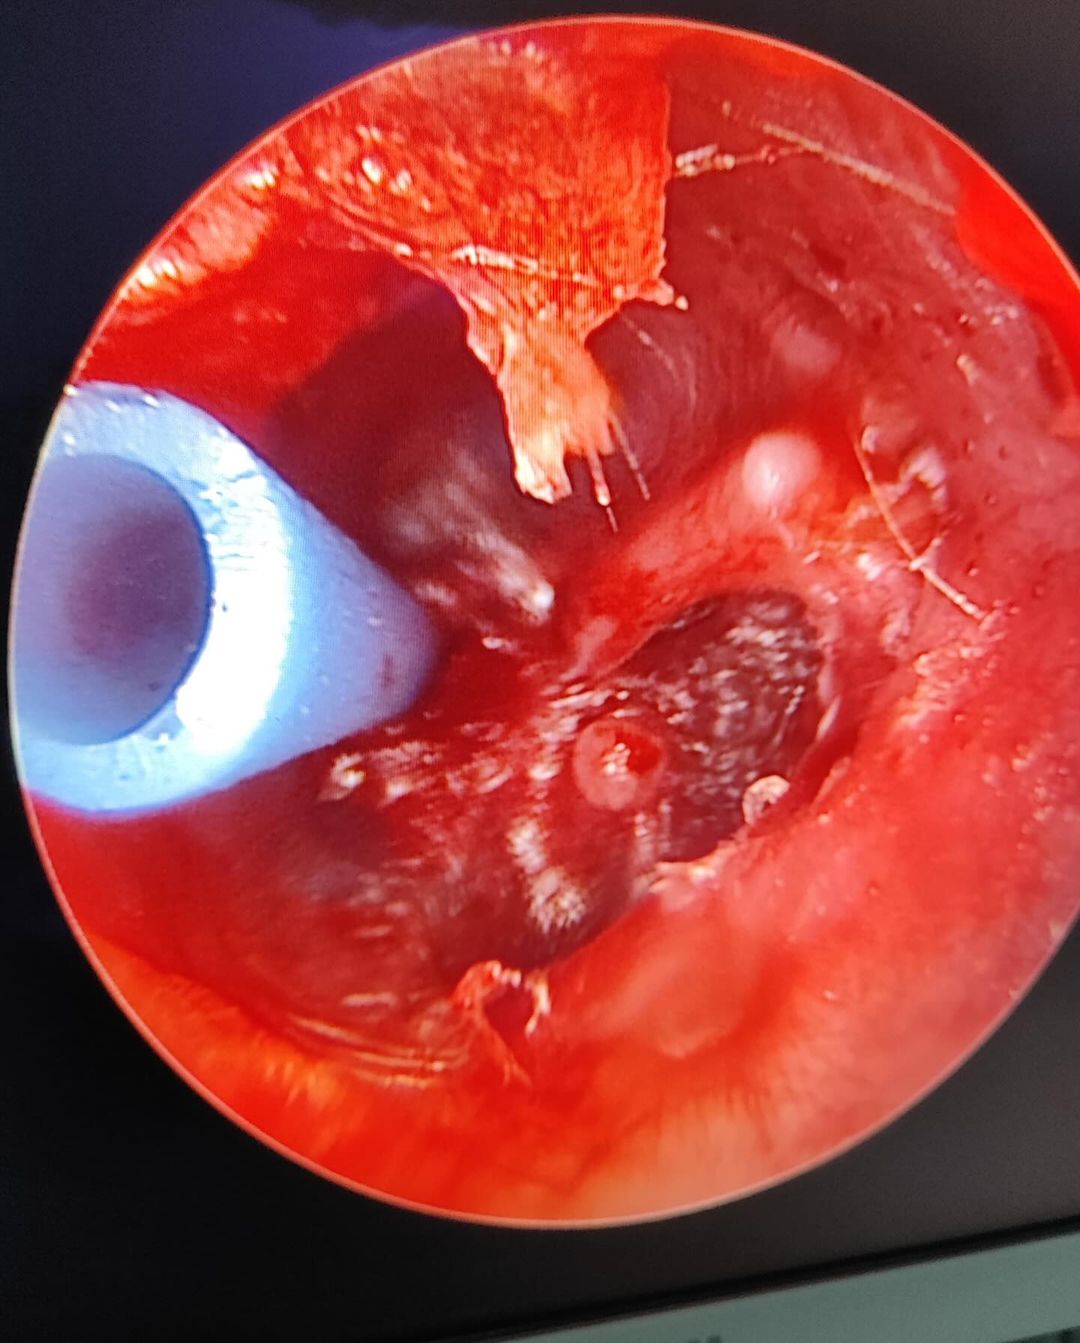

Tıbbi Resim Galeri